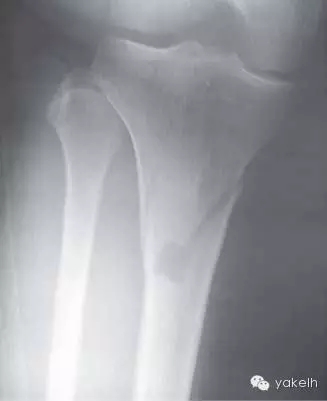

¤¤中等麻藥鎮(zhèn)痛劑可很好緩解脛骨取骨的術(shù)后疼痛。供區(qū)遠(yuǎn)端腿部的瘀斑很常見。該區(qū)域的取骨手術(shù)很少發(fā)生并發(fā)癥,可能會發(fā)生的并發(fā)癥有血腫形成、傷口裂開、感染、骨折。盡管很少,大部分脛骨骨折是由于腿部取骨位置過低而引起的(圖13.14)。

圖13.14 由于腿部取骨位點過低,導(dǎo)致少見的脛骨骨折。